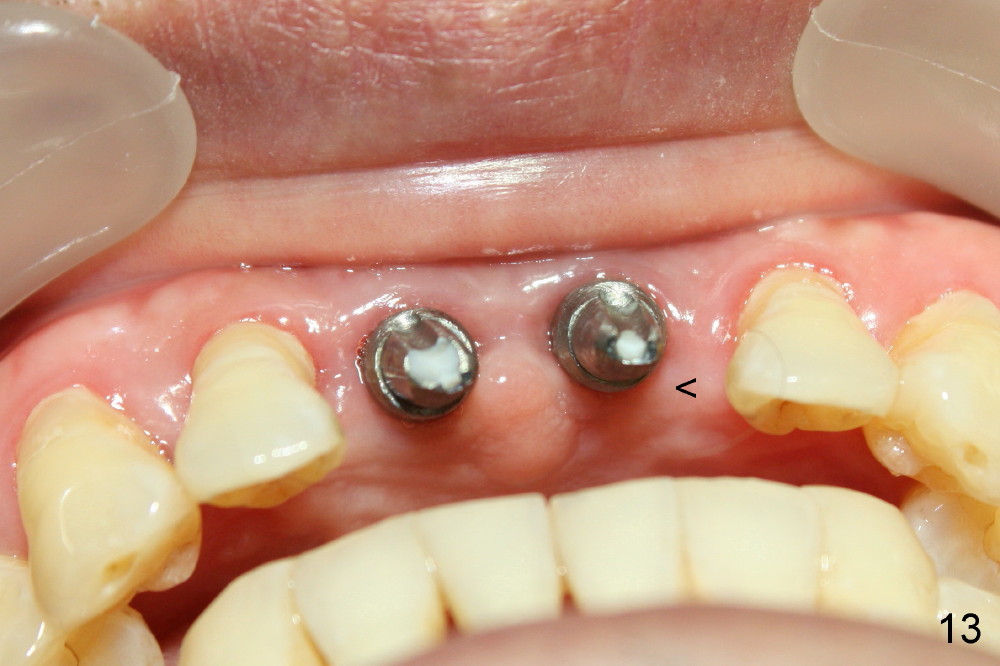

The patient returns for follow up one month and a half after implant surgery. The gingiva around the implants looks healthy. No infection relapses (Fig.12,13: <).